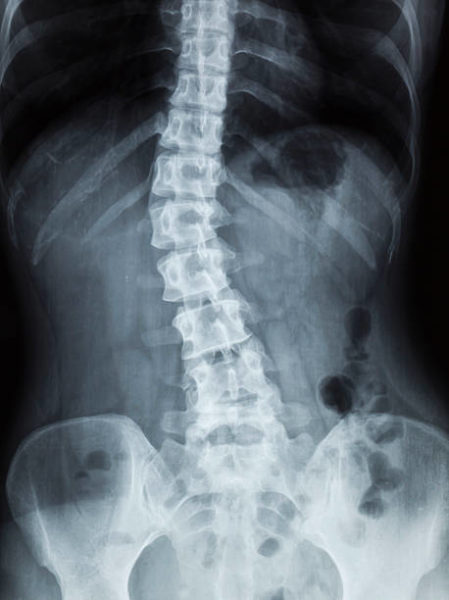

La scoliose se caractérise par une déviation permanente de la colonne vertébrale. En effet, les déformations commencent souvent à la puberté et se poursuivent après la fin de la croissance. Si on ne peut soigner une scoliose, on peut empêcher son évolution.

La scoliose se distingue de l’attitude scoliotique par une déformation tridimensionnelle de la colonne vertébrale. Quand le patient se penche en avant (test du plongeur) une gibbosité apparaît. Dans le cas d’une attitude scoliotique, il n’y a pas de rotation des vertèbres. Elle peut être due par exemple à des jambes de longueurs différentes et à un bassin déséquilibré.

La scoliose est souvent asymptomatique, non douloureuse, mais implique des soins de kinésithérapie, d’ostéopathie et d’orthopédie à vie. Une collaboration entre ces trois professionnels donne généralement de bons résultats. Les semelles orthopédiques participent alors à freiner l’avancement de la scoliose. Elles évitent aussi les compensations qui elles, peuvent provoquer des douleurs : lombalgies, cervicalgies, dorsalgie, etc. Il existe différents types de scolioses impliquant différents traitements posturaux. Il existe des scolioses thoraciques, lombaires et des doubles scolioses.